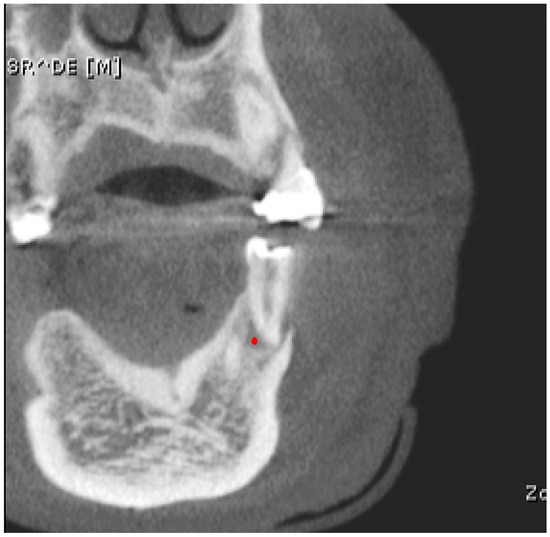

Next, a second evaluator well-versed in CBCT image analysis who was unaware of clinical and diagnostic information conducted the texture analysis. The BMP format images were imported into MaZda software (version 4.6) for texture feature calculation. A circular region of interest (ROI) of 44 pixels in diameter was manually delineated at the center of the lesion (point marked in red) on the frontal image to ensure that only the lesion tissue was included (

Figure 1). The center of the periapical lesion was determined at the intersection of the lateromedial and superoinferior lines.